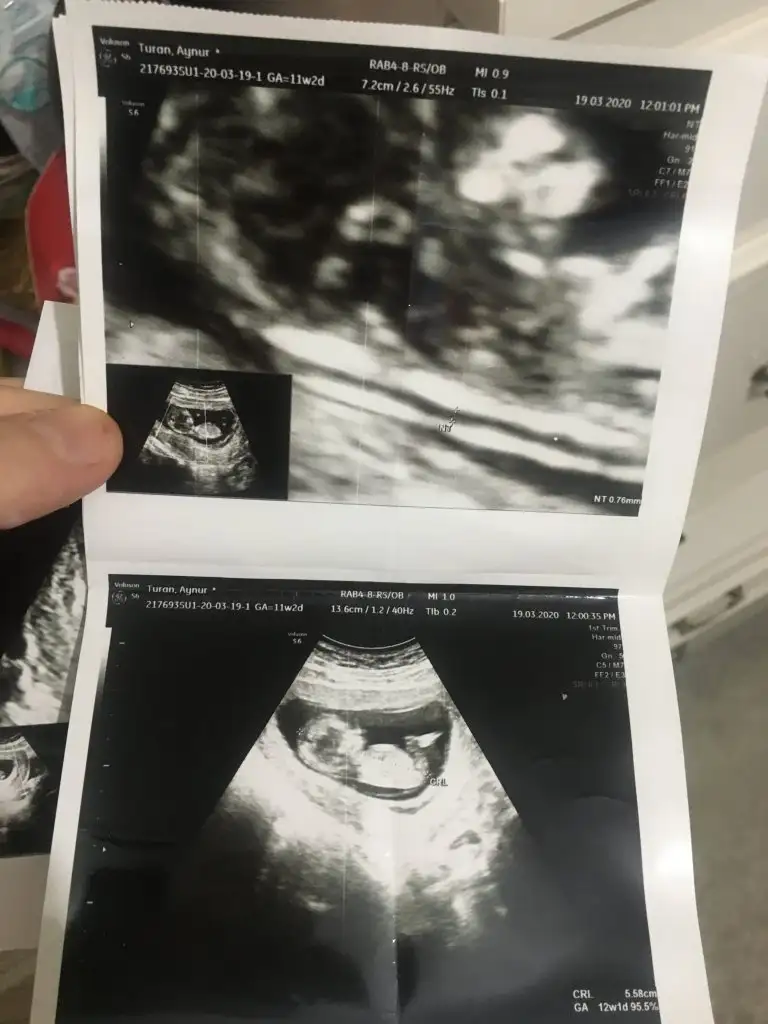

Net değilKizlar kim yorumluyor burda nub teorisini..Ben 18.hafta icindeyim gerci ama hala ogrenemedim cinsiyetini beninkinede bakarmisiniz bu da eksik kalmasınburda 12+2 gunluk videoda cektim goruntuyu tam bu bolge sanirim baktiginiz

Nubu ne dik nede paralel tam karşıya bakıyor nubu böyle usgler yanıtıyor beni başka usg varmı nubu erkek desem erkek gib tam dik değilBen de yorum istiyoruuum12+2 burdaEki Görüntüle 2633538

Sanki kız gibi emin olamıyorum çok net değil beyaz usg başka varsa paylaşın 11 12 de olabilirEki Görüntüle 2633651 13 haftalık nub bakarmısınz rica etsem

degilmi ne pekiO nub değilbaşka usg varsa paylaşın 11 12 13 haftalar olabilir

İlk sayfada usgler var bakın istersenizdegilmi ne pekidoktorumda yanlıs gormuş demek